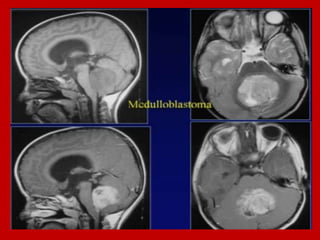

CT and MRI of medulloblastoma.

CT and MRI of medulloblastoma

Medulloblastoma.